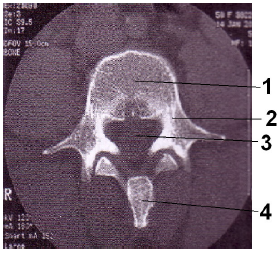

Assinale a alternativa que apresenta, na seqüência correta, as estruturas anatômicas identificadas na imagem abaixo.

Assinale a alternativa que representa, em ordem crescente, as estruturas assinaladas na imagem tomográfica anteriormente apresentada.